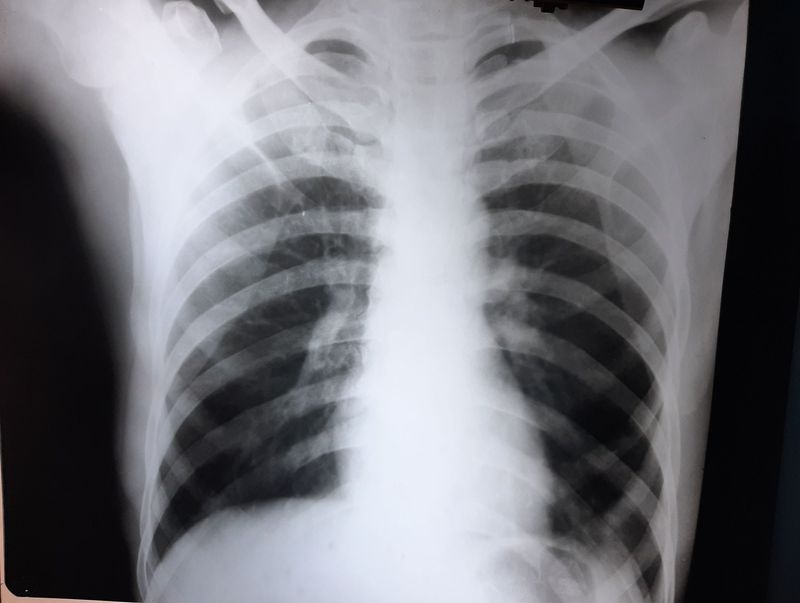

35 yr old male having complain of hemoptysis since 15 days,mild fever seen. Hx of smoking.

Mediastinitis